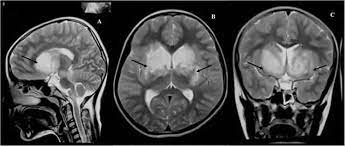

This activity reviews the evaluation and treatment of KBS and highlights. IN 1937 Klüver and Bucy 1 described a striking behavioral syndrome in rhesus monkeys after bilateral temporal lobe ablations. Kluver-Bucy syndrome KBS is a rare neuropsychiatric disorder due to lesions affecting bilateral temporal lobes especially the hippocampus and amygdala.

Klüver-Bucy syndrome is a rare behavioral impairment that is associated with damage to both of the anterior temporal lobes of the brain.